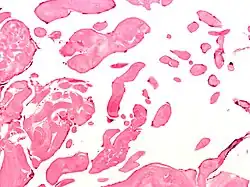

Low magnification micrograph of an excised aortic valve papillary fibroelastoma showing the characteristic avascular branching papillae, H&E stain

Papillary fibroelastoma are typically found and accurately diagnosed by imaging. The diagnosis is confirmed by pathology. Histologically, papillary fibroelastomas have branching avascular papillae, composed of collagen, that are covered by endothelium.